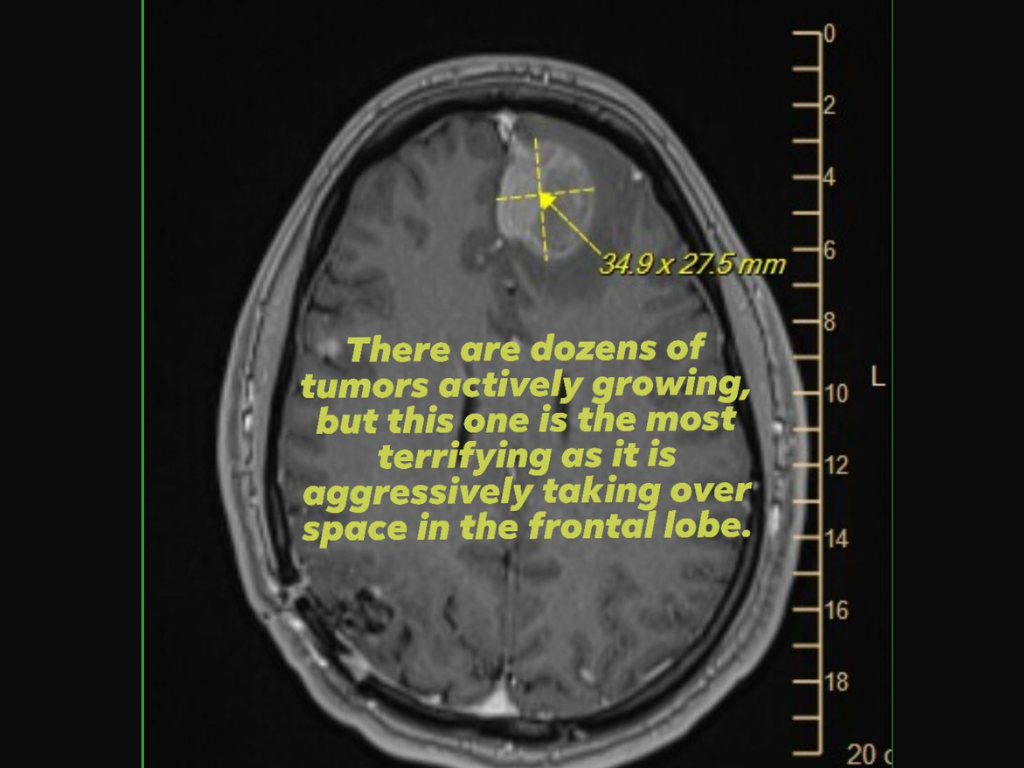

Como prueba, también adjuntó una imagen de un escáner cerebral (IRM) que mostraba un tumor agresivo del lóbulo frontal, al tiempo que suplicaba apoyo o ayuda a los ejecutivos de Epic Games, que tomaron las decisiones clave sobre los despidos.